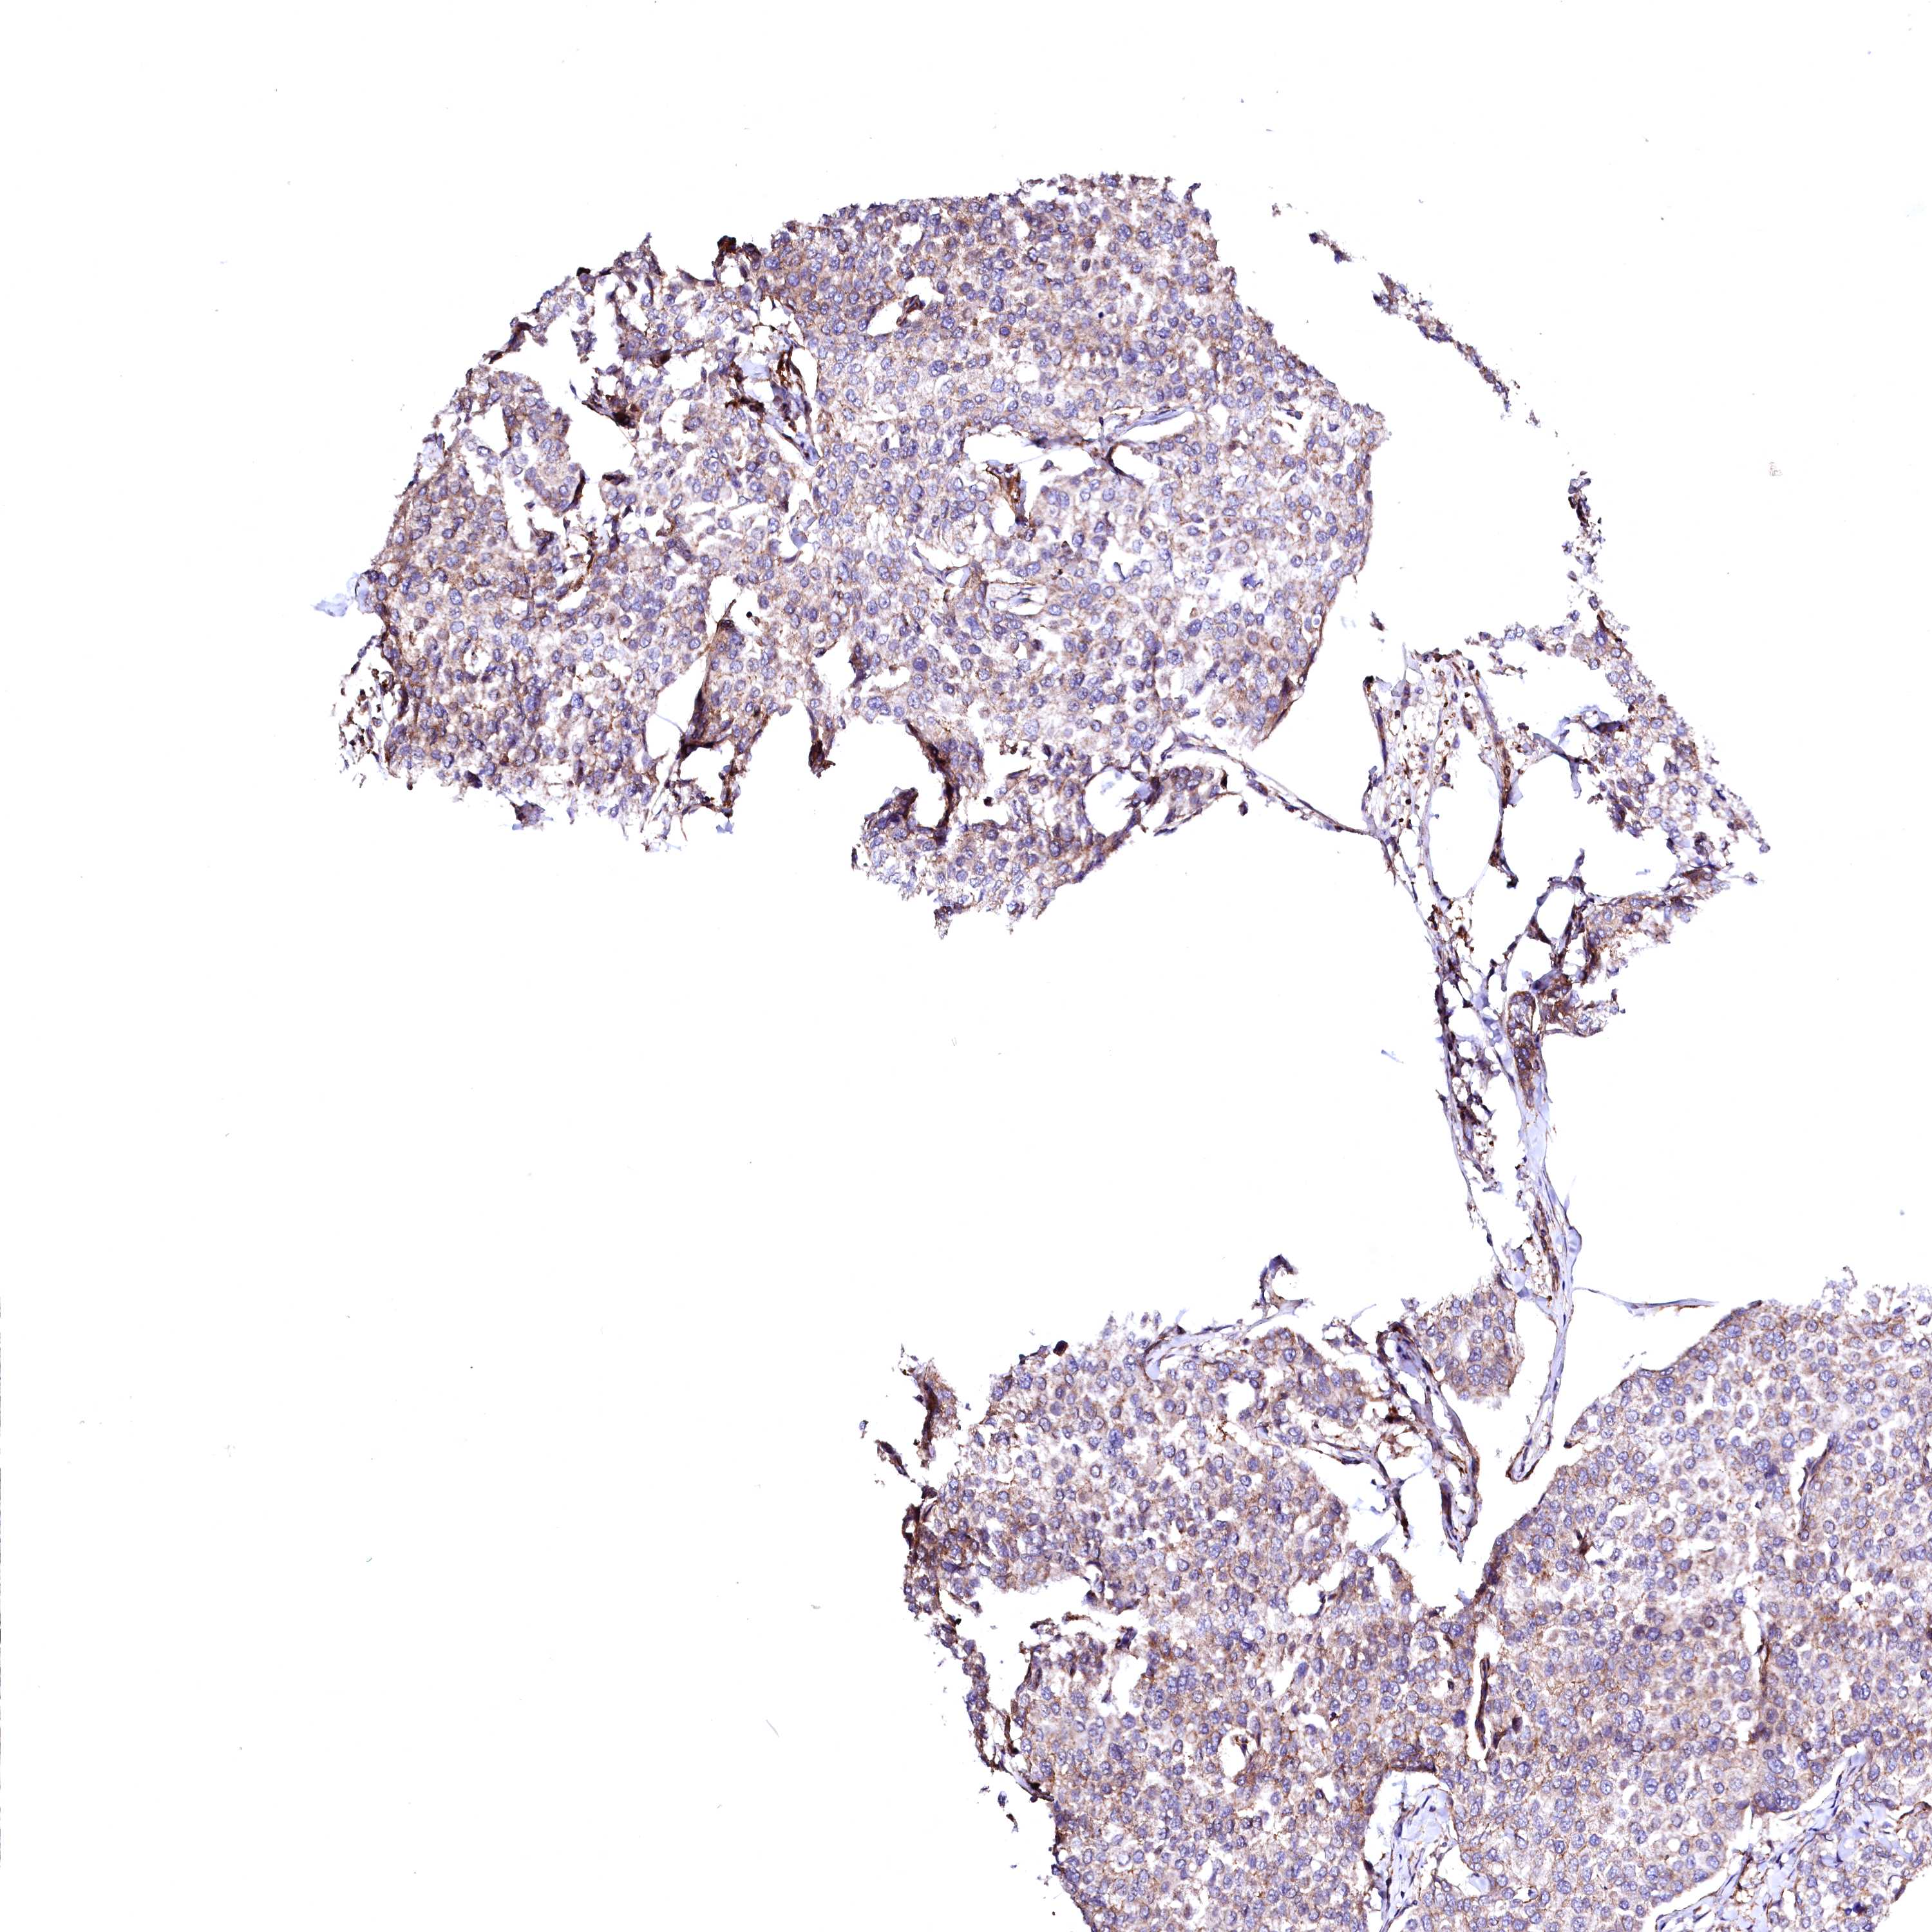

CANCER BREAST CANCER Show tissue menu

BRCA TCGA BRCA VALIDATION PROTEIN EXPRESSION